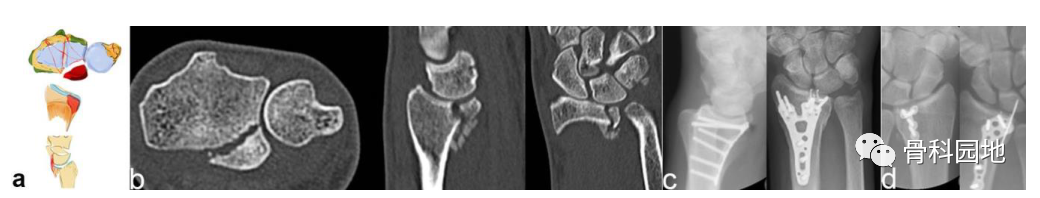

3、背侧关键骨块施加在背侧方向的作用力不仅会导致桡骨背侧骨折, 而且还会使腕关节背侧脱位。

注:背侧脱位,背侧外部插入。手掌韧带断裂(a)。普通 X 射线显示背侧脱位的程度。然而,在 CT 扫描中,可以看到关节面的额外凹陷、S 状切迹的台阶和背键骨块 (b)。背侧骨块不一定是关键骨块。如左两个图像所示。尽管背侧脱位,但掌侧骨折块仍附着在掌侧韧带装置上,这个由骨韧带组成的掌侧关键骨折块需要特别注意,必须首先固定,如图所示(c)